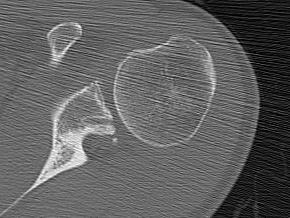

CT

Hill Sachs lesion / posterior bony bankart / glenoid retroversion

Reverse Hill Sachs / Posterior bony Bankart / Glenoid retroversion

Critical posterior glenoid bone loss

- compared successful posterior labral surgery with unsuccessful

- 11% glenoid bone loss - 10 x failure rate

- 15% glenoid bone loss - 25 x failure rate